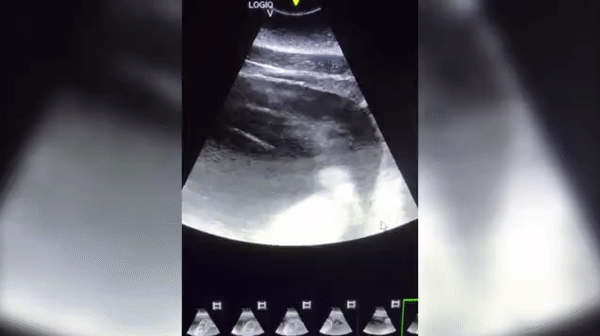

미국의 한 해양테마공원 측이 흰고래로도 불리는 벨루가 암컷 한 마리가 임신했다는 소식을 전하며 어미 배 속에서 새끼가 움직이고 있는 모습을 담은 보기 드문 초음파 영상을 공개해 화제다.

KSAT 등 현지매체 보도에 따르면, 텍사스주(州) 관광명소 '시월드 샌안토니오 지점'은 지난 11일(현지시간) 페이스북을 통해 암컷 벨루가 루나(Luna)의 배 속 태아를 촬영한 초음파 영상을 공개했다.

영상은 태아 상태의 새끼 벨루가가 움직일 때마다 그 머리와 눈 그리고 상반신 일부가 나타나는 모습을 담고 있다.

이에 대해 공원 측은 “어미는 ‘허즈번드리 트레이닝’(husbandry training)으로 불리는 특수 훈련을 받은 덕분에 수의팀이 검사하는 동안 가만히 있을 수 있어 초음파 영상을 기록할 수 있었다”고 설명했다. 허즈번드리 트레이닝은 동물원 등에서 멸종 위기에 처한 동물 등을 보존하기 위한 노력의 일부분으로 행하는 훈련 방법을 말한다.

공원 측은 또 “우리는 루나의 임신 소식을 공유하게 돼 매우 기쁘고 앞으로 새끼 벨루가를 시월드 가족으로 맞이할 날을 기대하며 어미를 24시간 내내 보살필 계획”이라고 밝혔다. 초음파 영상 속 새끼 벨루가는 오는 가을쯤 태어날 예정이다.